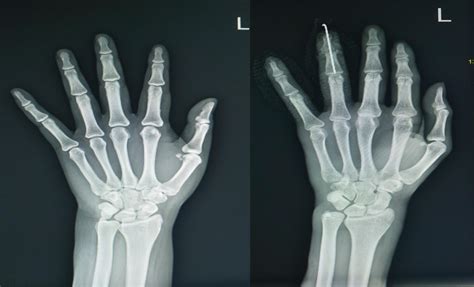

Getting an X Ray Normal Hand is a quick and painless process. You will typically be asked to place your hand flat on the image receptor. The technologist will likely capture the hand in a few different angles, most commonly the posteroanterior (PA), oblique, and lateral views. These multiple angles are crucial because a single view might hide a fracture that overlaps with another bone.

View Purpose

Posteroanterior (PA) Provides a standard overview of the carpal, metacarpal, and phalangeal bones.

Oblique Helps visualize the overlapping bones of the mid-hand and reduces superimposition.

Lateral Essential for assessing the alignment of the joints and identifying displaced fractures.